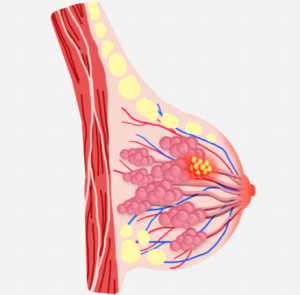

Breast nodules typically refer to lumps or masses found in the breast. Most of these nodules are benign (non-cancerous). Some common benign causes include breast infections, fibroadenomas, simple cysts, fat necrosis, fibrocystic changes, and intraductal papillomas.

However, a small percentage of breast nodules can be malignant (cancerous), and they may exhibit the following warning signs:

- Size: Larger nodules tend to raise concerns more easily.

- Shape: Nodules with irregular or jagged edges have a higher likelihood of malignancy.

- Texture: If a nodule feels hard or has an uneven texture upon touch, further investigation is needed. This is especially important for women over 50 years old, as the risk of malignancy increases with age.